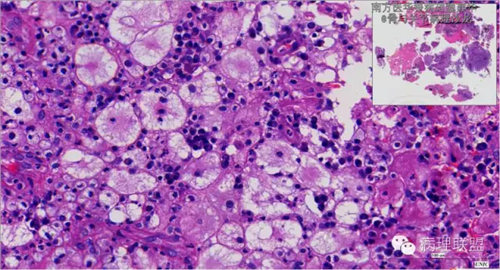

来源于组织细胞的相似性骨病ECD vs RDD 看图说话

病例由南方医华银病理魏建华提供,致谢。